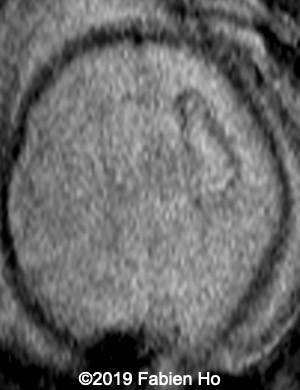

Axial T2*w: T2* sequence is used in this case for its susceptibility to magnetic field inhomogeneity, i.e. to iron deposits for example. It is used to depict hemosiderin, which is roughly oxidized blood, i.e. “aged” blood. Blood MRI signal evolves as time passes.

6

7